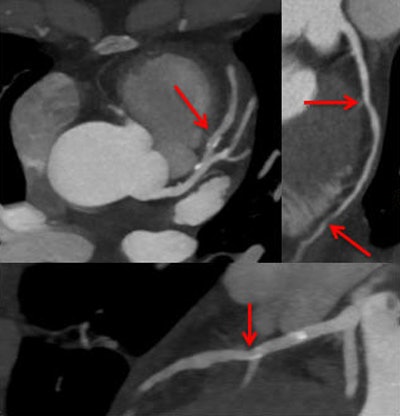

Cardiac dual-energy CT study in progress evaluates the potential of increasing coronary CT angiography's (CCTA) specificity by combining anatomic imaging and myocardial rest iodine distribution. Above, stenosis in intermediate left anterior descending (LAD) artery on morphologic CCTA images. Below, minor iodine distribution within distal LAD territory is a sign of hemodynamic significance of the lesion. Images courtesy of Dr. Thomas Henzler.

Cardiac dual-energy CT study in progress evaluates the potential of increasing coronary CT angiography's (CCTA) specificity by combining anatomic imaging and myocardial rest iodine distribution. Above, stenosis in intermediate left anterior descending (LAD) artery on morphologic CCTA images. Below, minor iodine distribution within distal LAD territory is a sign of hemodynamic significance of the lesion. Images courtesy of Dr. Thomas Henzler.When creating MI images, previous studies have shown it's better to calculate the myocardial blood-flow ratio manually rather than using absolute myocardial flow to calculate the effects of the stenosis. Calculating the myocardial blood-flow ratio better differentiates myocardium at risk, and could have other potential benefits.